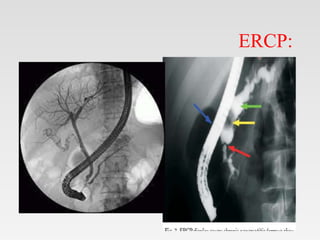

ERCP:

• Provides the most accurate visualization of the

pancreatic ductal system and has been

regarded as the criterion standard for

diagnosing chronic pancreatitis.

• Findings include characteristic “chain of

lakes” beading of the main pancreatic duct,

and intraductal filling defects.